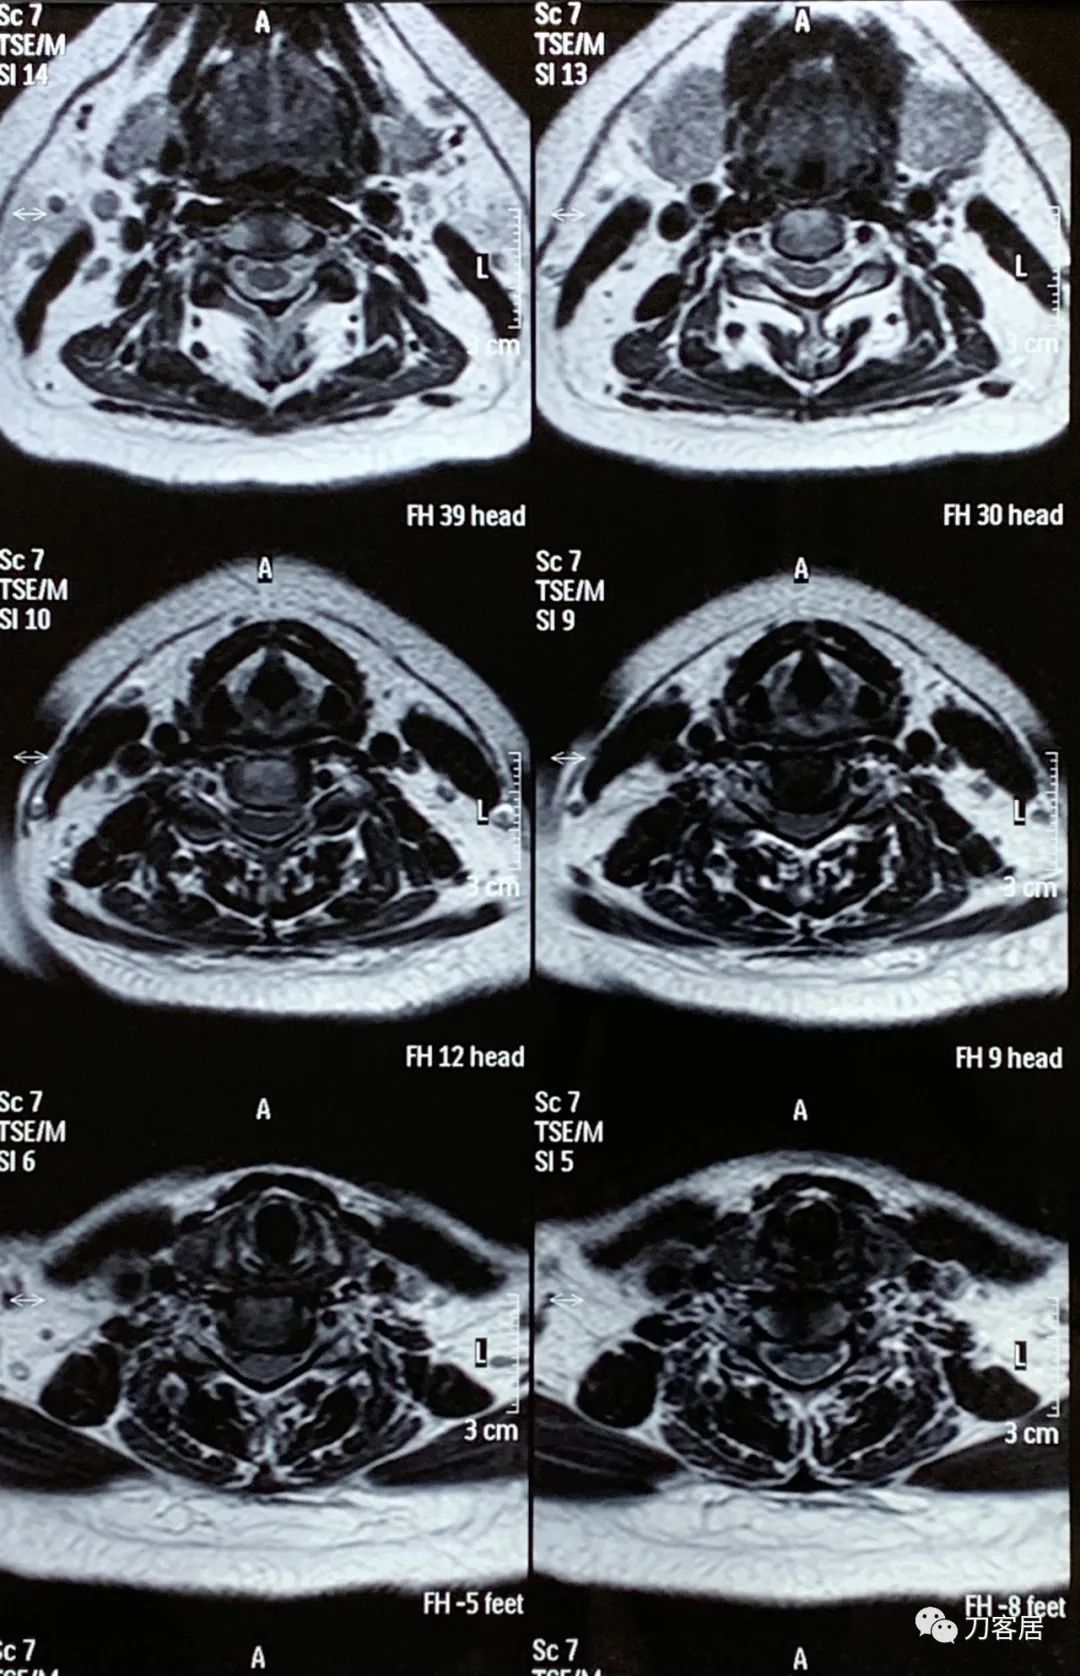

图13. 20200525平凉安康医院颈椎MRI01

图14. 20200525平凉安康医院颈椎MRI02

图15. 20200525平凉安康医院颈椎MRI03

图16. 20200525平凉安康医院颈椎MRI04

图17. 20200525平凉安康医院颈椎MRI报告

2020年5月25日做的颈椎MRI并没有新的发现,仍然是颈3-6椎间盘变性及轻度突出,颈6-7椎间盘变性并膨出,颈椎生理曲度不稳,局部反弓。